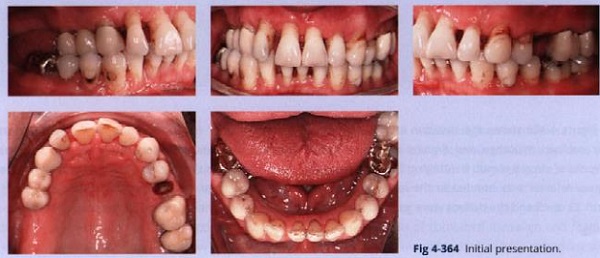

Người đàn ông lớn tuổi này có tình trạng xương bị tiêu với răng trồi và những khoảng ở cả hai cung (hình 4-364).

Bệnh nhân có những dấu hiệu của CMD với lệch vị trí đĩa về phía trước mà không trở lại vị trí và đau đầu.

• Viêm quanh răng

• Cắn sâu và mất sự hỗ trợ phía sau ở tương quan tâm

• Răng chen chúc